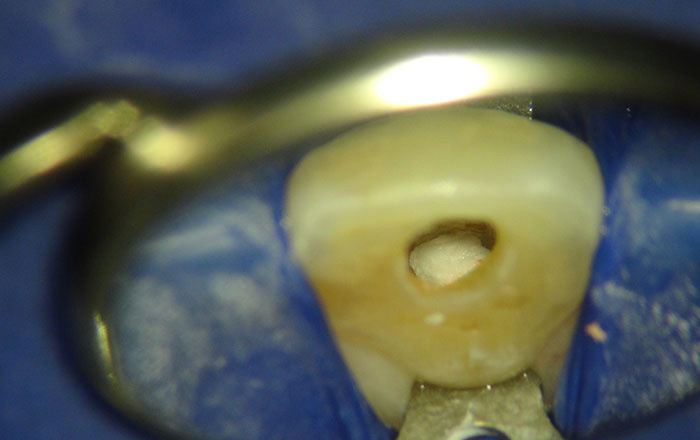

ウォーキングブリーチは、神経の治療をした後、黒く変色した歯の歯髄腔に、歯を白くする薬剤を入れて、歯を内側から漂白するホワイトニング方法です。

3.ウォーキングブリーチの方法

ウォーキングブリーチの手順は、以下の通りです。

1)根っこの治療(根管治療)がきちんと行われたのを確認する

2)歯髄腔に、薬剤を止めるための封をする

3)歯髄腔に薬剤を入れる

過酸化水素水・過ホウ酸ナトリウムが混合された30〜35%の濃度のペーストを入れます。

4)封をする

5)歯科用レジンで蓋をする

CRという、歯科用のレジンで蓋をします。

6)1週間に1回薬剤を交換し、写真撮影を行う